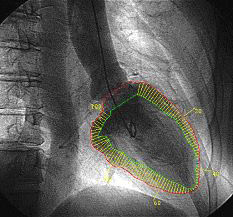

検査結果例(狭心症例 Bull’s Eye像)

-

運動時

9時~2時の範囲の外周(心基部)の中心部(心突部)までに渡って、血流が低下しています。

安静時

血流が低下していた部位が回復しています。

運動-安静時

安静時と運動時の差を示した図です。

9時~2時の範囲に差があるのが分かります。

特に1時~2時の範囲で顕著にあらわれています。